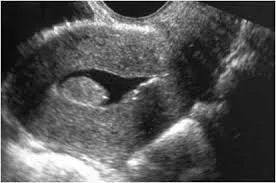

Saline Infusion Sonography (SIS)

SIS is basically an ultrasound performed after a little saline (salt water) has been injected into the uterine cavity via a fine plastic catheter that is passed through the cervix.

A small amount of saline (salt water) is injected through the catheter. The saline allows accurate assessment of the uterine cavity. The saline dilates the uterine cavity slightly and outlines the lining of the uterus well, making it easier to assess the endometrium accurately and detect certain pathology like polyps.